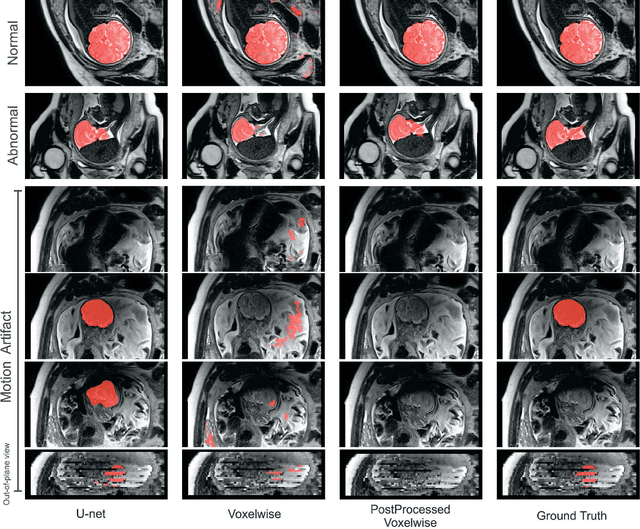

Abstract:Brain segmentation is a fundamental first step in neuroimage analysis. In the case of fetal MRI, it is particularly challenging and important due to the arbitrary orientation of the fetus, organs that surround the fetal head, and intermittent fetal motion. Several promising methods have been proposed but are limited in their performance in challenging cases and in real-time segmentation. We aimed to develop a fully automatic segmentation method that independently segments sections of the fetal brain in 2D fetal MRI slices in real-time. To this end, we developed and evaluated a deep fully convolutional neural network based on 2D U-net and autocontext, and compared it to two alternative fast methods based on 1) a voxelwise fully convolutional network and 2) a method based on SIFT features, random forest and conditional random field. We trained the networks with manual brain masks on 250 stacks of training images, and tested on 17 stacks of normal fetal brain images as well as 18 stacks of extremely challenging cases based on extreme motion, noise, and severely abnormal brain shape. Experimental results show that our U-net approach outperformed the other methods and achieved average Dice metrics of 96.52% and 78.83% in the normal and challenging test sets, respectively. With an unprecedented performance and a test run time of about 1 second, our network can be used to segment the fetal brain in real-time while fetal MRI slices are being acquired. This can enable real-time motion tracking, motion detection, and 3D reconstruction of fetal brain MRI.